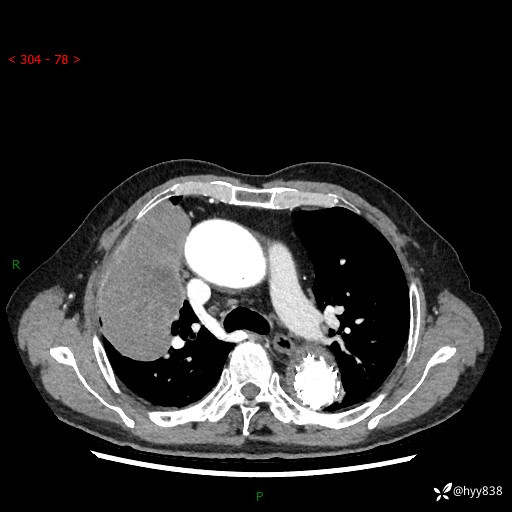

静脉期